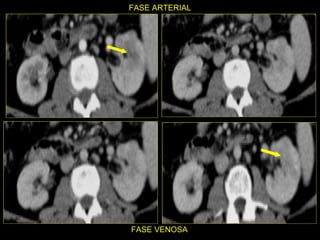

Caso # 5 ♀ ,  5ta década de la vida Antecedente de cirrosis hepática, hepatitis C y  Diabetes Mellitus. Ingresa con dolor abdominal por lo que se realiza estudio de TC en cortes axiales y coronales, fases arterial y venosa.

Hallazgos Caso # 5 Área hipodensa en tercio medio del riñón izquierdo, sugestiva de lesión neoplásica a descartar área de inflamación focal.

SE INICIA ANTIBIOTICOTERAPIA Y SE INDICA ESTUDIO DE CONTROL A LOS 5  MESES.

Hallazgos estudio de control Caso # 5: La lesión ha desaparecido, lo que fue indicativo de que  se trataba de proceso inflamatorio focal resuelto posterior a manejo medico.